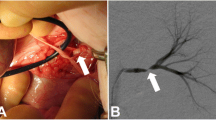

Our results show that SSFP Unenhanced-MRA is capable of yielding consistent diagnostic quality renal artery angiographic images (Figs. 2a,b & 3a,b). Analysis of images showed that even the quality of renal artery delineation in its intrarenal peripheral branches was comparable or better than CE-MRA in diagnostic quality (Figs. 2a,b & 4).

The inherent nature of Unenhanced-MRA techniques offers valuable advantages over CE-MRA beyond that of avoiding the administration of gadolinium contrast agents. By not using contrast media, problems with errant bolus timing, venous contamination of images and renal parenchymal enhancement are removed. Equally, an Unenhanced-MRA study can be easily repeatable if circumstances require whilst a non-breath-hold technique often allows diagnostic imaging to be obtained in patients who cannot hold their breath for a conventional CE-MRA setting which is a particularly important advantage. It has been noted that the intraparenchymal renal vessels can often be better demonstrated and delineated on Unenhanced-MRA [12] (Figs. 2a,b and 4). Our anecdotal observations support this finding but whether this is of significant clinical value is unsubstantiated at present.